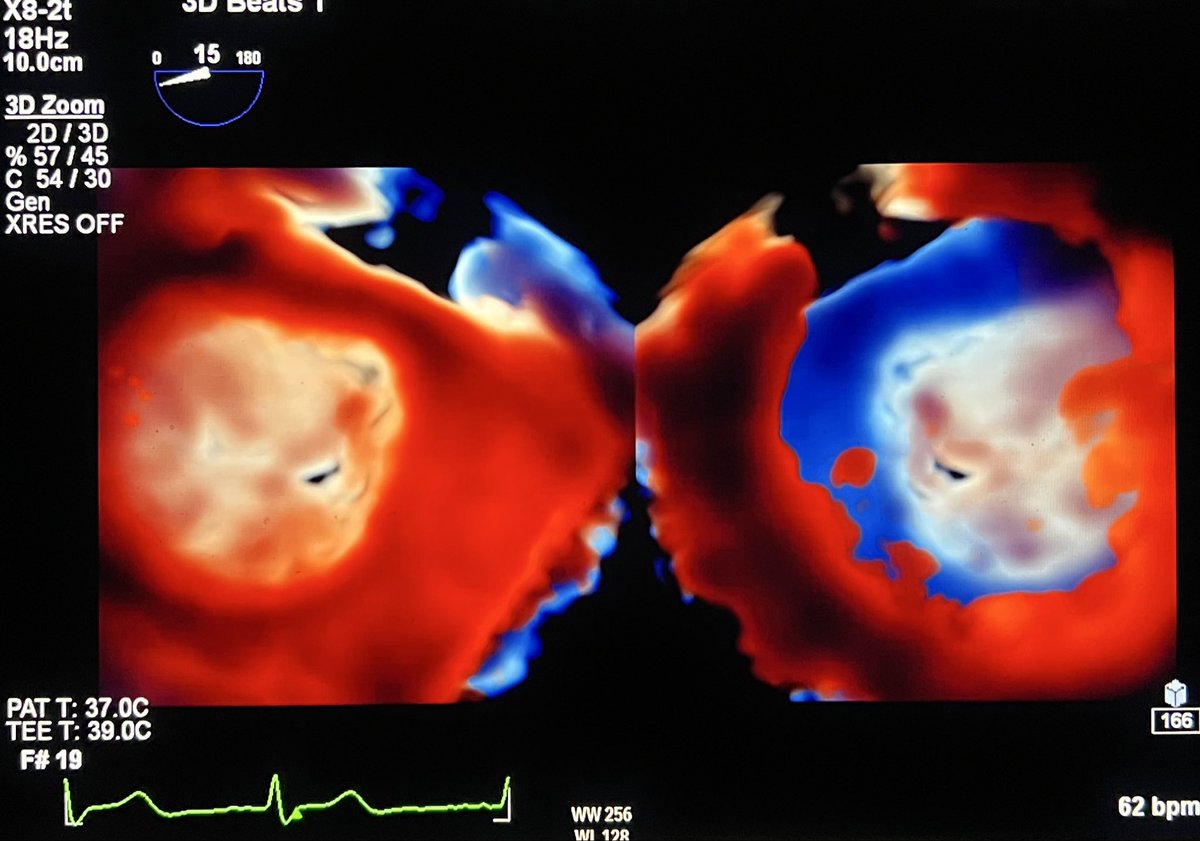

#echofirst ✅ Transillumination (TL) 3D of MV⬇️ ✅ Example of the unique contribution of TL in showing anatomical & tissue details ✅ Cleft at P2P3⬇️ @MarcoSa52466127 @NMerke @argulian @iamritu @PWesslyMD @PWengrofskyMD @alex1708ander @DrRajeshG1 @bwoody58 @KemalogluOz